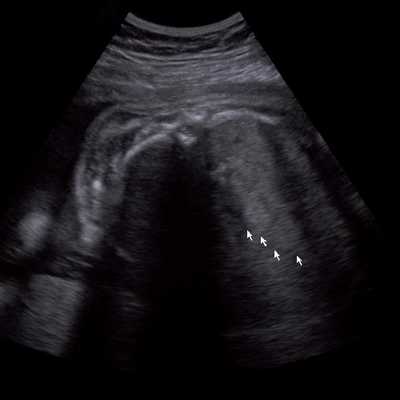

Под диафрагмой справа визуализировалось гиперэхогенное опухолевидное образование несколько неоднородной солидной структуры, с четкими ровными контурами, размером 50x38x35 мм. К нижнему полюсу данного образования прилежала правая почка, имеющая нормальные размеры, форму и структуру. Нижняя полая вена была смещена кпереди и влево. Обращала на себя внимание выраженная гепатомегалия, причем структура печени не была однородной. Она содержала множественные гиперэхогенные включения размерами до 17 мм, окруженные тонким гипоэхогенным периферическим ободком. Цветовое допплеровское картирование(ЦДК) демонстрировало интенсивную периферическую васкуляризацию опухоли (рис. 1-3).

Рис. 1. Нейробластома правого надпочечника плода. Беременность 31 нед 4 дня.

Рис. 2. Кровоток в нейробластоме плода. Цветовое допплеровское картирование. Отчетливо виден питающий сосуд, огибающий образование по его периферии. К нижнему полюсу образования прилежит интактная почка плода.

Рис. 3. Метастазы в печени плода. Поперечное сечение брюшной полости плода. Гепатомегалия. В структуре печени плода определяются округлые включения несколько повышенной эхогенности (стрелки), с гипоэхогенным ободком - метастазы.